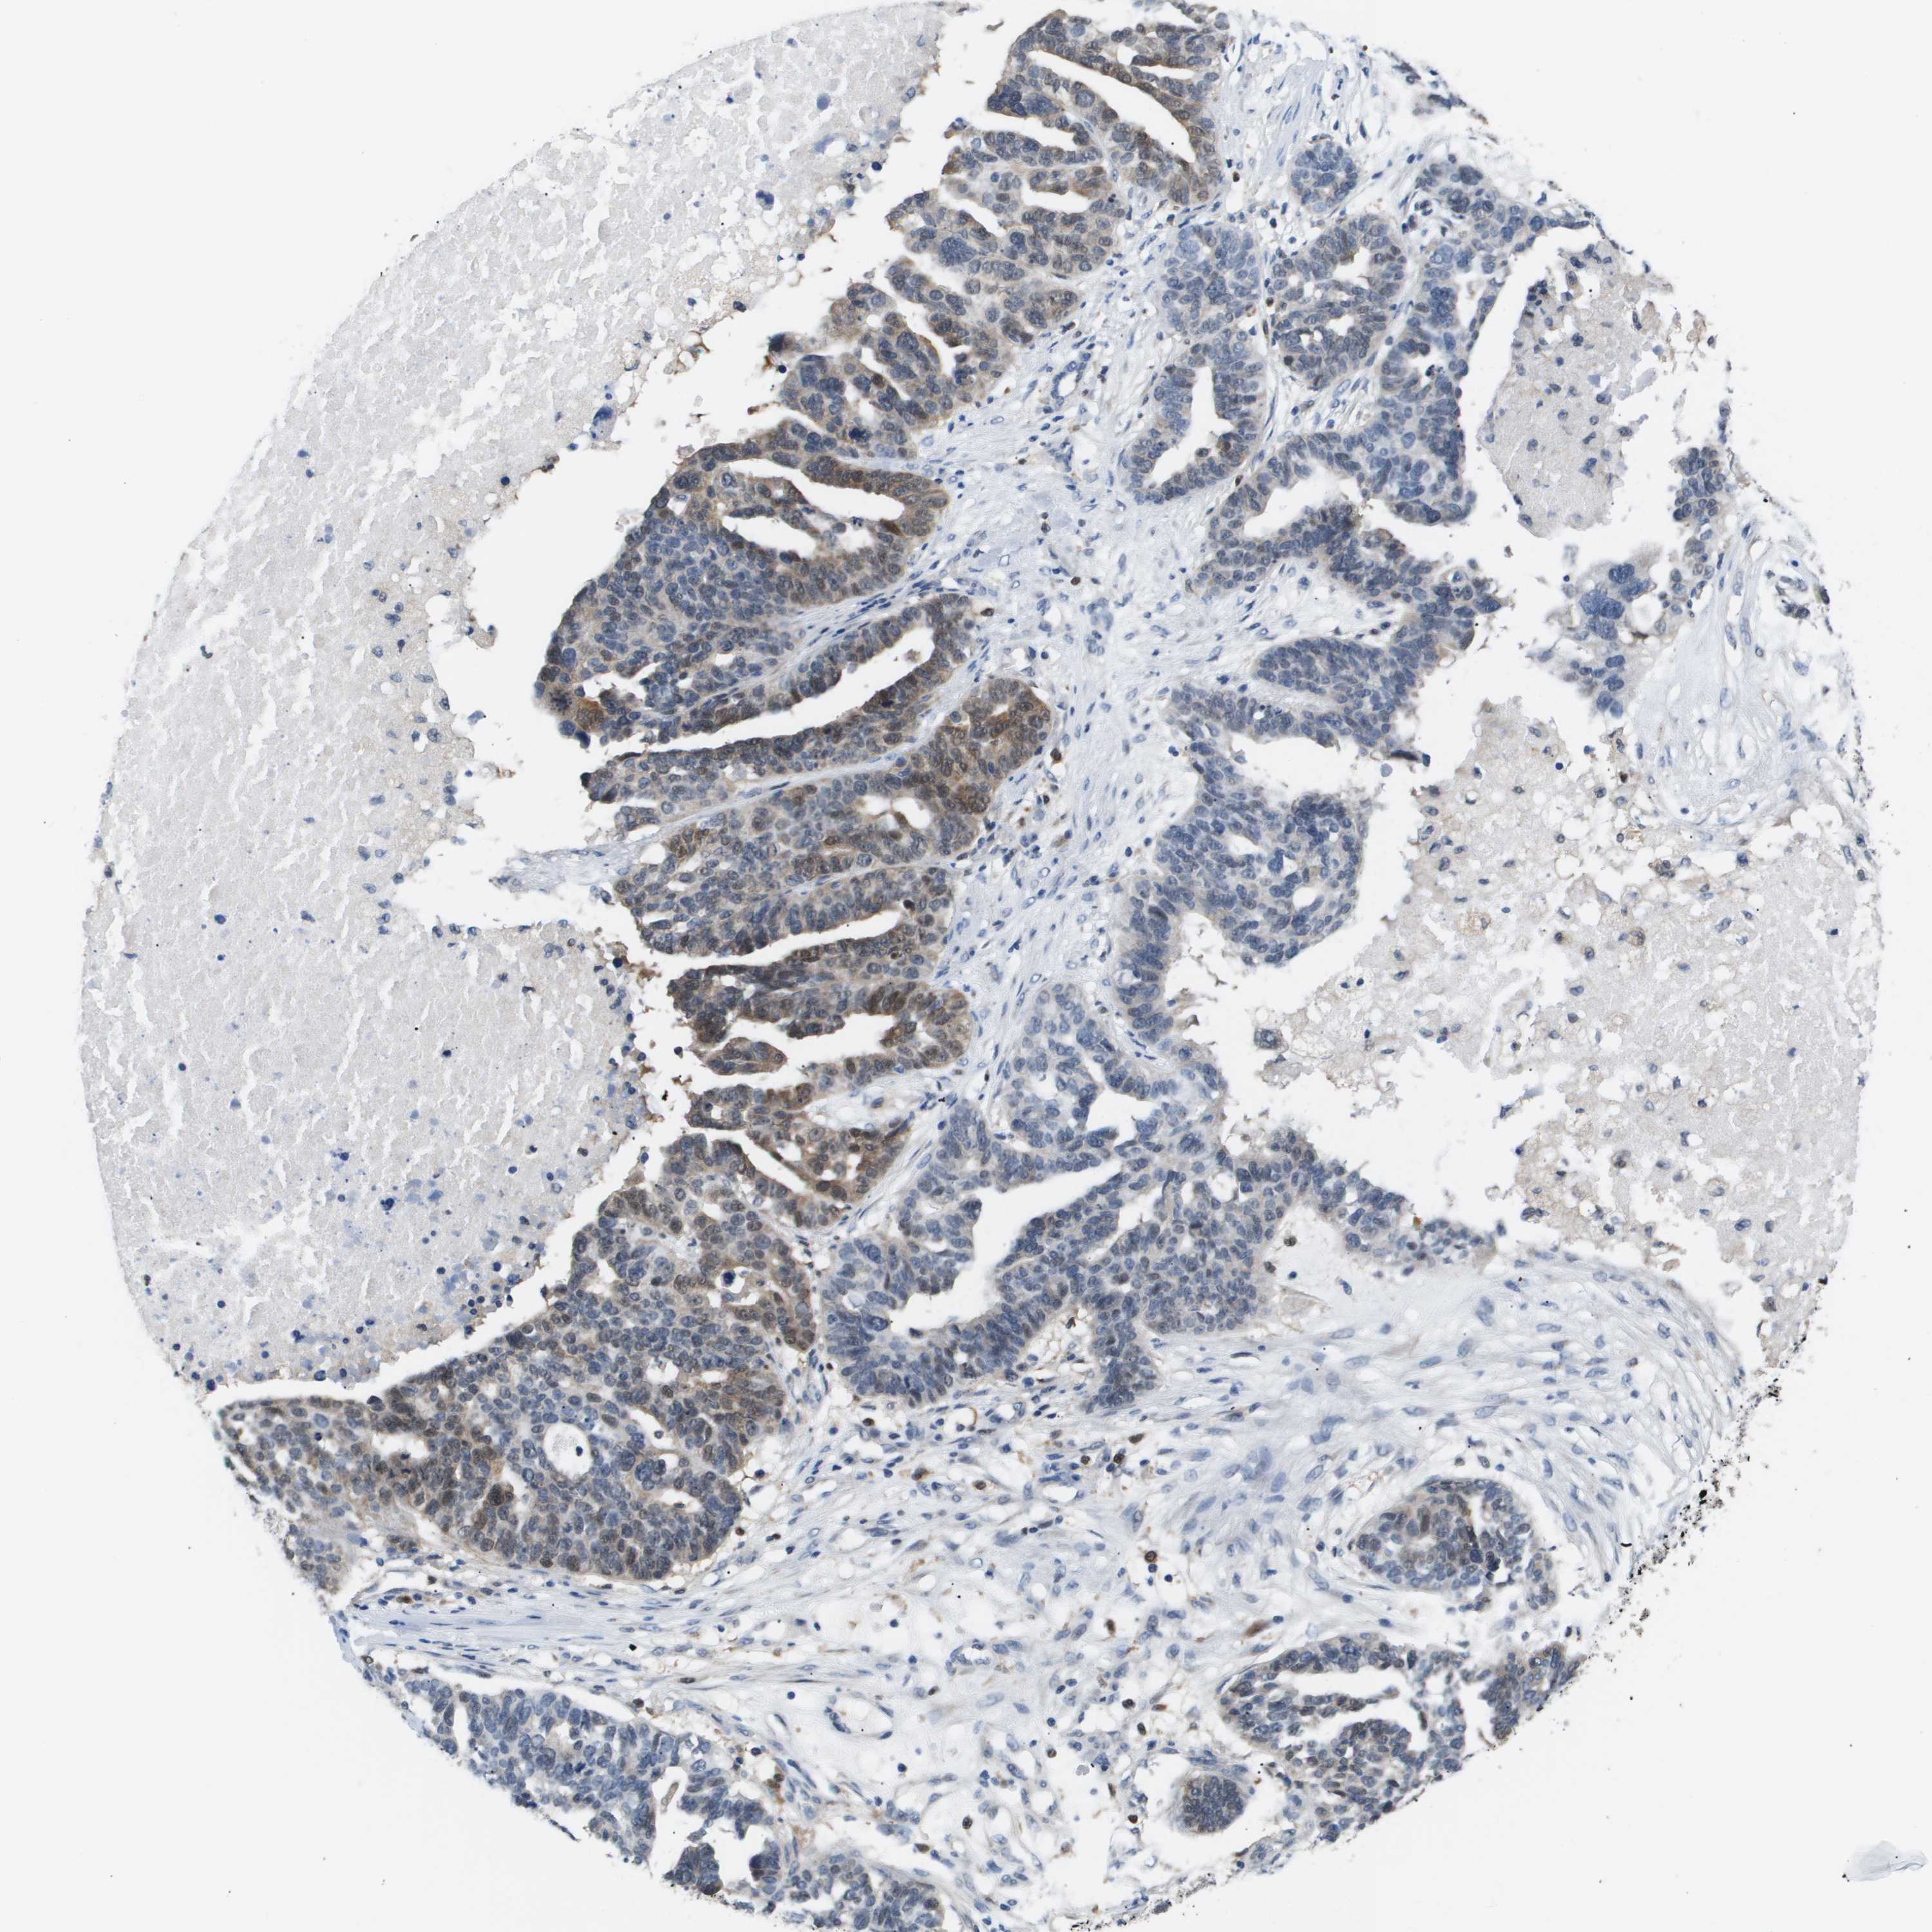

OVARIAN CANCER - Protein expressioni

A mouse-over function shows sample information and annotation data. Click on an image to view it in a full screen mode. Samples can be filtered based on level of antibody staining by selecting one or several of the following categories: high, medium, low and not detected. The assay and annotation is described here.

Note that samples used for immunohistochemistry by the Human Protein Atlas do not correspond to samples in the TCGA dataset.

Antibody stainingi

Antibody staining in the annotated cell types in the current human tissue is reported as not detected, low, medium, or high, based on conventional immunohistochemistry profiling in selected tissues. This score is based on the combination of the staining intensity and fraction of stained cells.

Each image is clickable and will lead to virtual microscopy that enables deeper exploration of all samples and also displays staining intensity scores, fraction scores and subcellular localization as well as patient and tissue information for each sample.

Antibody HPA017919

Antibody HPA019649

Antibody HPA027734

Antibody CAB006246

Staining

High

Medium

Low

Not detected

Intensity

Strong

Moderate

Weak

Negative

Quantity

>75%

75%-25%

<25%

None

Location

Nuclear

Cytoplasmic/membranous

Cytoplasmic/membranous,nuclear

Cystadenocarcinoma, serous, NOS

Carcinoma, endometroid

Cystadenocarcinoma, mucinous, NOS

Carcinoma, NOS